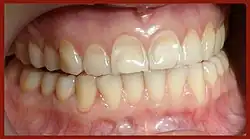

видимые маркёры процессов костной резорбции

У женщин, имеющих в анамнезе какие-либо из перечисленных факторов, при снижении уровня эстрогенов развиваются некариозные поражения зубов (эрозии, клиновидные дефекты, повышенная стираемость). Эта патология характеризуется убылью (часто — видимой) твёрдых тканей зубов (эмали, дентина и цемента), которая часто сопровождается их повышенной чувствительностью (гиперестезией зубов).[4]:53

"Зубы являются составной частью костного скелета, к тому же единственной его видимой частью. Общие механизмы в развитии некариозных поражений зубов, остеопении и остеопороза возникают у женщин вследствие снижения базового уровня эстрогенов в крови. Однако остеопения и остеопороз развиваются медленно и бессимптомно, и зачастую диагностируются только в поздние сроки, а некариозные поражения имеют сигнальные симптомы в виде дефектов тканей и гиперестезии зубов, которые легко обнаруживаются и сами себя проявляют. Таким образом, они наглядны, — чем оказывают неоценимую помощь врачу в диагностике.[7]:153

В свете новейших научно-медицинских исследований на стыке стоматологии, эндокринологии и остеологии некариозные поражения зубов могут выступать в качестве сигналов тревоги, предупреждающих о системных гормонально-метаболических нарушений, а также выявляющих на ранних стадиях риск развития остеопении и остеопороза у женщин. Кроме того их проявление следует расценивать как ранний диагностический признак остеопении, а женщины, имеющие некариозные поражения зубов, автоматически входят в группу риска развития остеопороза.[7]:152-153